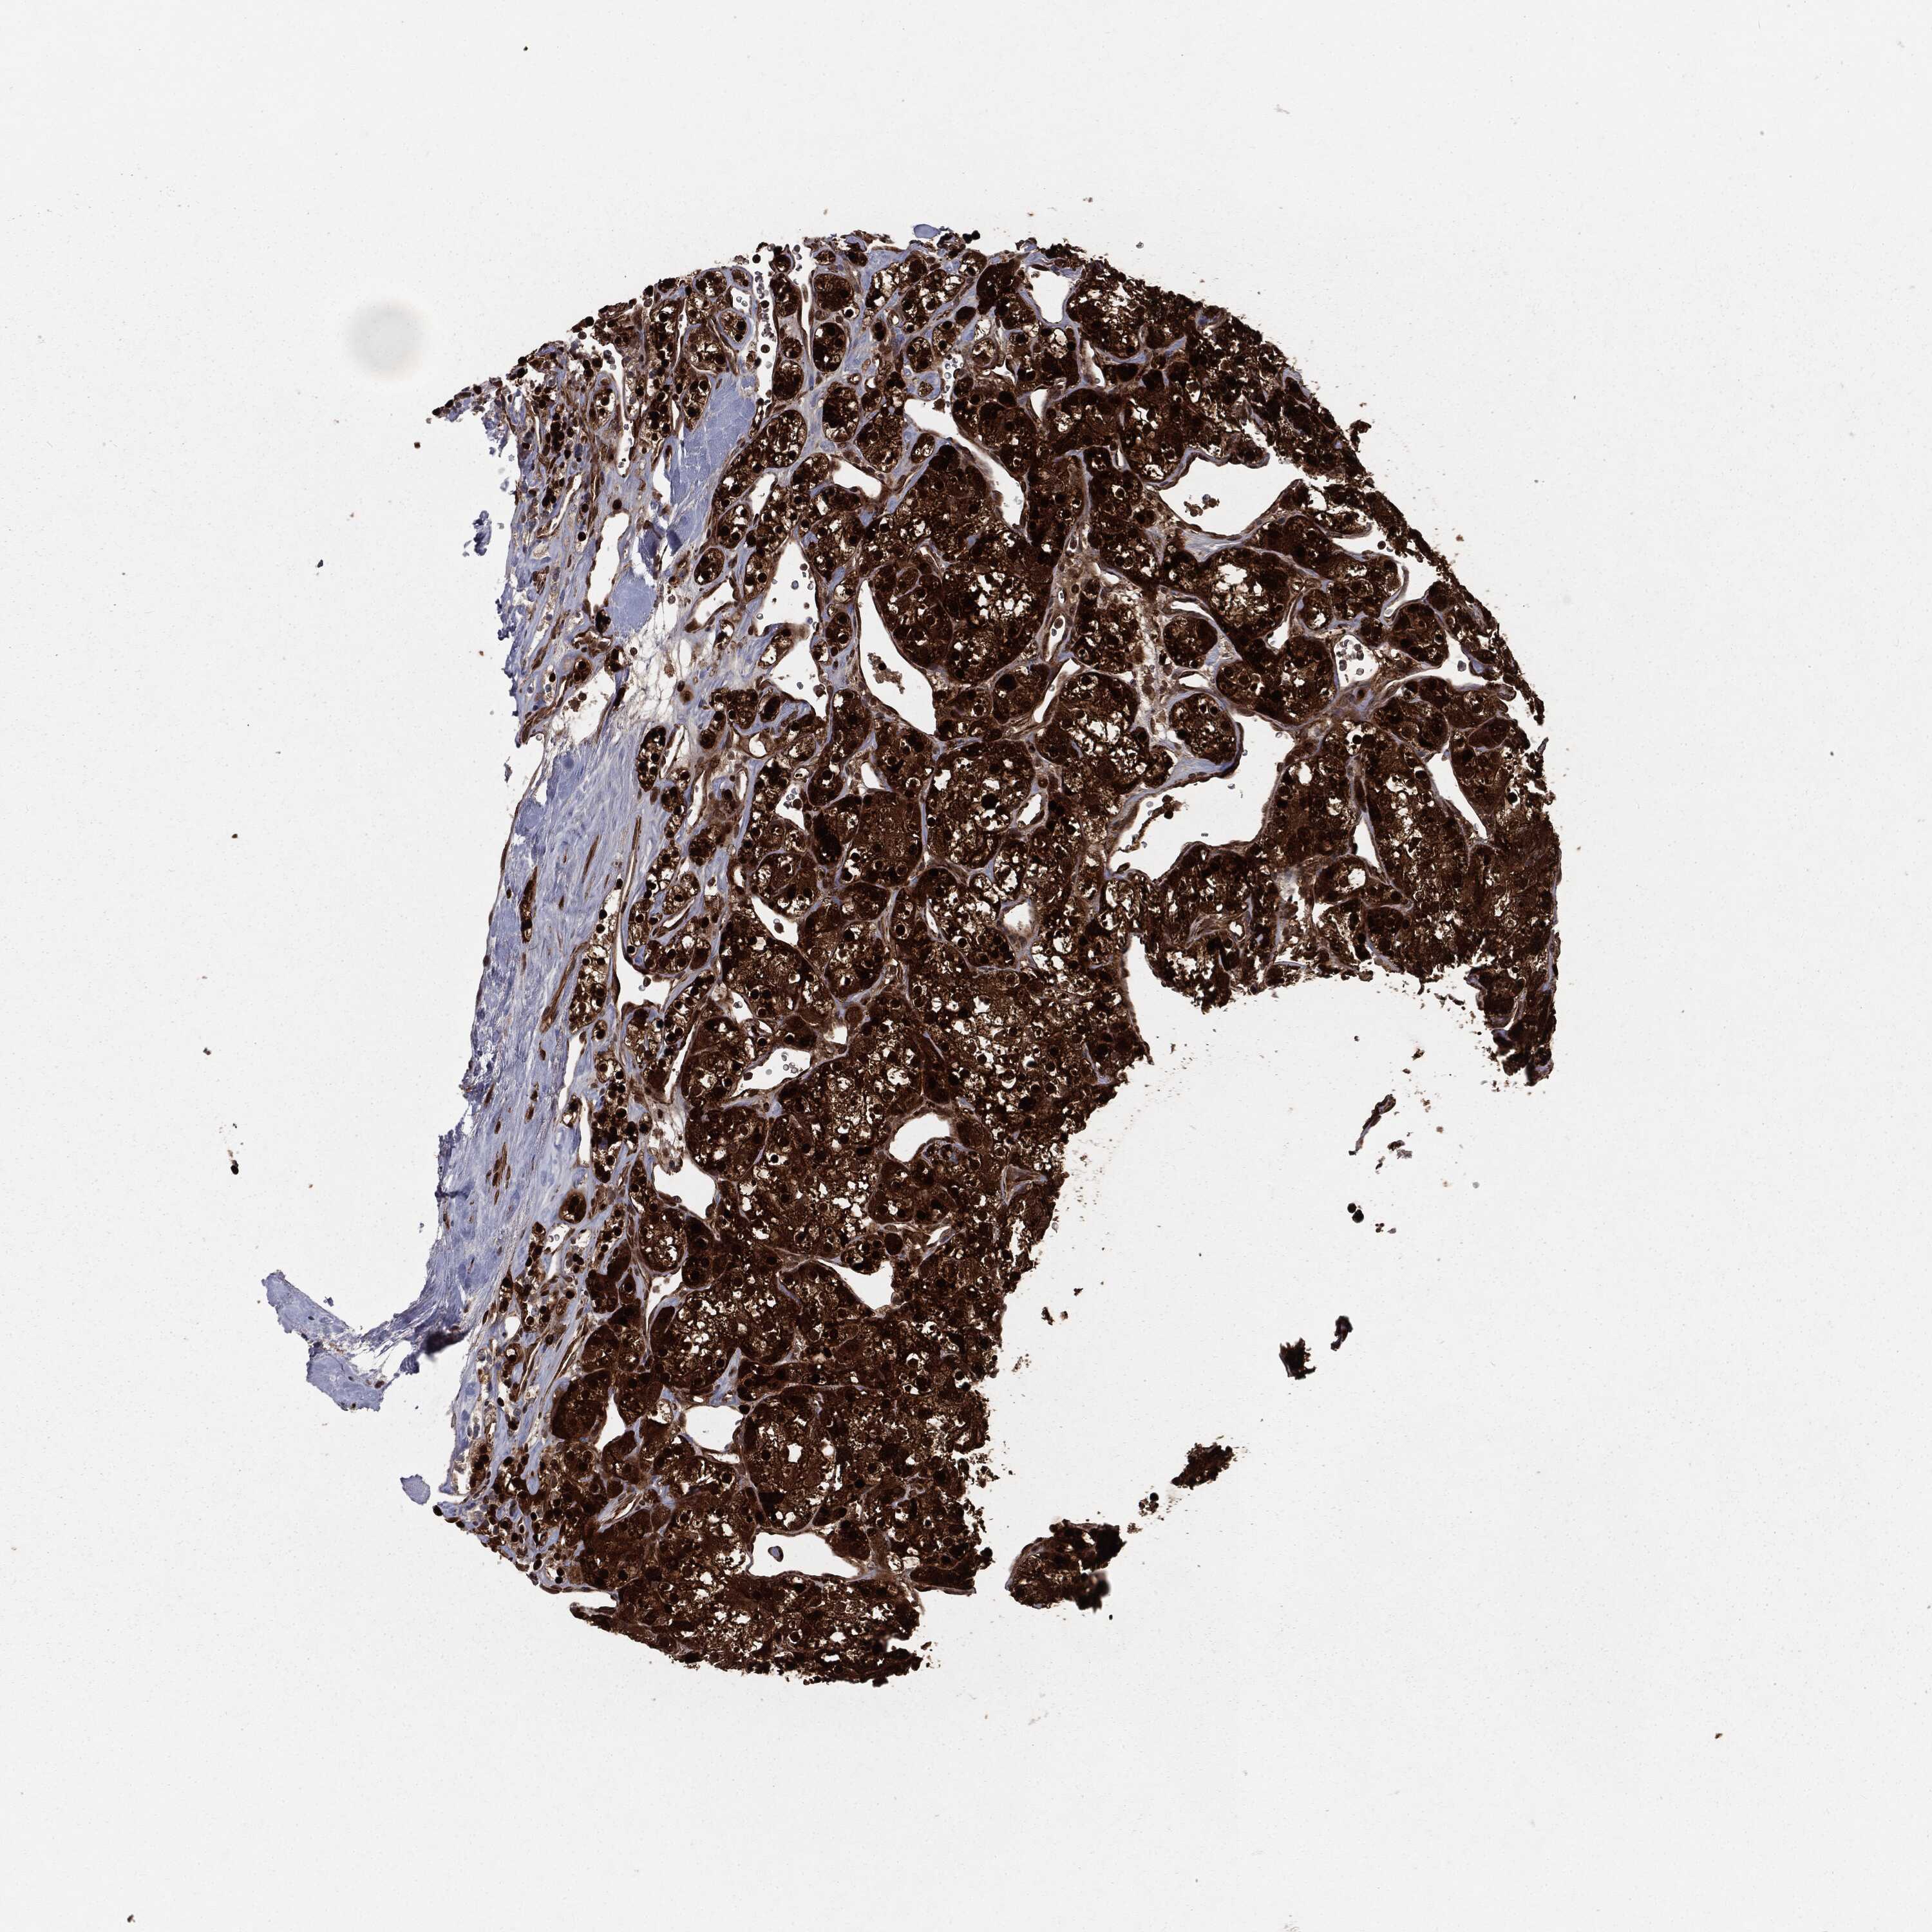

KIDNEY RENAL CLEAR CELL CARCINOMA (TCGA) - Interactive survival scatter ploti

The Survival Scatter plot shows the clinical status (i.e. dead or alive) for all individuals in the patient cohort, based on the same data that underlies the corresponding Kaplan-Meier plots. Patients that are alive at last time for follow-up are shown in blue and patients who have died during the study are shown in red.

The x-axis shows the expression levels (FPKM) of the investigated gene in the tumor tissue at the time of diagnosis. The y-axis shows the follow-up time after diagnosis (years). Both axes are complimented with kernel density curves demonstrating the data density over the axes. The top density plot shows the expression levels (FPKM) distribution among dead (red) and alive patients (blue). The right density plot shows the data density of the survived years of dead patients with high and low expression levels respectively, stratified using the cutoff indicated by the vertical dashed line through the Survival Scatter plot. This cutoff is automatically defined based on the FPKM cutoff that minimizes the p-score. The cutoff can be changed by dragging the vertical line or by entering a cutoff value in the square labeled "Current cut-off".

Under the Survival Scatter plot the p-score landscape (black curve; left axis) is shown together with dead median separation (red curve; right axis). Dead median separation is the difference in median mRNA expression between patients who have died with high and low expression, respectively. It is calculated as follows: median FPKM expression of dead patients with high expression - median FPKM expression of dead patients with low expression. This is intended to aid the user in visually exploring custom cutoffs and the associated p-scores and dead median separation.

Individual patient data is displayed and can be filtered by clicking on one or more of the category buttons on the top of the page. Categories describing expression level and patient information include: high, low, alive, dead, female, male and tumor stages. The scale of the x-axis can be toggled between linear and log-scale by clicking on the "x log" button. Mouse-over function shows TCGA ID, patient information and mRNA expression (FPKM) for each patient.

& Survival analysisi

Kaplan-Meier plots summarize results from analysis of correlation between mRNA expression level and patient survival. Patients were divided based on level of expression into one of the two groups "low" (under cut off) or "high" (over cut off). X-axis shows time for survival (years) and y-axis shows the probability of survival, where 1.0 corresponds to 100 percent.

RANBP9 is potential prognostic, high expression is favorable in Kidney Renal Clear Cell Carcinoma (TCGA)

Best expression cut offi

Based on the FPKM value of each gene, patients were classified into two groups and association between prognosis (survival) and gene expression (FPKM) was examined. The best expression cut-off refers the FPKM value that yields maximal difference with regard to survival between the two groups at the lowest log-rank P-value. Best expression cut-off was selected based on survival analysis .

When clicking on this number, the vertical dashed line indicating cut-off, the interactive survival plot, and the Kaplan-Meier curve will be adjusted to show results based on the best expression cut-off.

: 11.37

TCGA RNA samplesi

RNA-seq data is reported as average FPKM (number Fragments Per Kilobase of exon per Million reads), generated by the The Cancer Genome Atlas (TCGA) .

Normal distribution across the dataset is visualized with box plots, shown as median and 25th and 75th percentiles. Points are displayed as outliers if they are above or below 1.5 times the interquartile range. FPKM values of the individual samples are presented next to the box plot.

Average pTPM 15.1

Number of samples 521